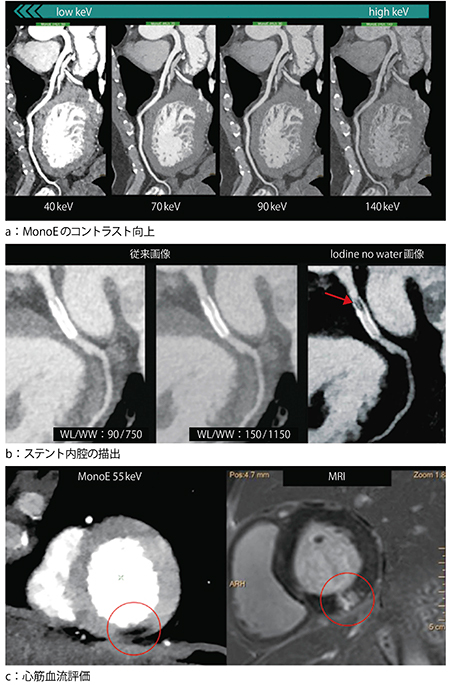

日常の心臓検査において,最適な造影コントラストを得られない場面がある。原因の多くは患者状態や撮影タイミングが考えられる。従来,CT装置においてこのケースは,再撮影による造影剤追加や被ばくの増加が伴い,患者負担の増大が懸念されていた。IQonでは,スペクトラルイメージングを用いることで,追加撮影なしでレトロスペクティブに造影効果を向上させ,診断に適した画像が提供可能となる。SBIから作成される仮想単色X線画像(以下,MonoE画像)では,エネルギーを40keVから200keVまで連続的に可変して表示することができる(図2 a)。低エネルギー領域の画像(以下,低keV画像)では,ヨード造影剤のコントラストを大幅に向上させ,予期せぬ造影不良のリカバリーを行うことができる。

2.確信度が向上したステント内腔の評価

術後のステント内腔評価は従来CTの画像診断において大きな課題の一つであった。その要因の一つがブルーミングアーチファクトと呼ばれるものであり,高い原子番号が素材に含まれるステントなどでしばしば発生する。この課題に対し,スペクトラルイメージングのIodine no water画像(以下,ヨード密度強調画像)は,アーチファクトを低減しステント内腔の視認性を劇的に改善することができる。図2 bで示すとおり,従来の120kVp画像ではアーチファクトの影響で内腔の評価は困難であり,ウインドウレベル(WL)やウインドウ幅(WW)の調整でも画質を改善することはできなかった。一方,ヨード密度強調画像ではアーチファクトの影響を低減し,ステント内腔の再狭窄(図2 b→)が明瞭に描出されている4)。

3.信頼性の高い心筋血流評価

冠動脈の形態的評価とともに,心筋血流評価を行う包括的な心臓検査が近年注目を浴びている。しかし,従来の120kVp画像ではビームハードニングアーチファクトの影響や造影コントラスト不足により,心筋血流評価を正確に行うことができない症例があった。それを解決する方法としてMonoE画像の使用が挙げられる。MonoEは,心筋近傍に位置する造影された大動脈や左心室からのビームハードニングアーチファクトを低減する効果があり,従来に比べ正確にCT値を表現し,より精度の高い心筋血流評価が可能になると考えられる。また,MonoEの低keV画像では心筋全体の造影コントラストを向上させるため,MR画像に匹敵するコントラストを得ることも可能であり,図2 cに示すとおり心筋血流低下を明瞭に描出している。さらに,ヨード密度強調画像では,各ピクセル値はヨード密度のmg/mLで示されるため,従来のCT値での評価に対し,より直接的かつ定量的に血流を評価することも可能となる。